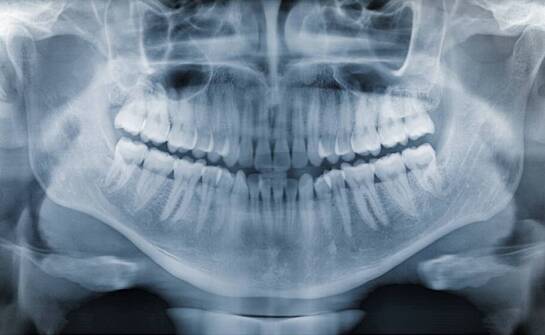

Jak RTG zębów wspiera leczenie stanów zapalnych w jamie ustnej?

RTG zębów to narzędzie w diagnostyce stomatologicznej, umożliwiające wykrywanie zmian w jamie ustnej. Z wykorzystaniem technologii obrazowania, takich jak tomografia stożkowa, lekarze mogą uzyskać szczegółowe obrazy anatomiczne, co wspiera proces leczenia. Uzyskane informacje mogą ułatwiać dobór dal